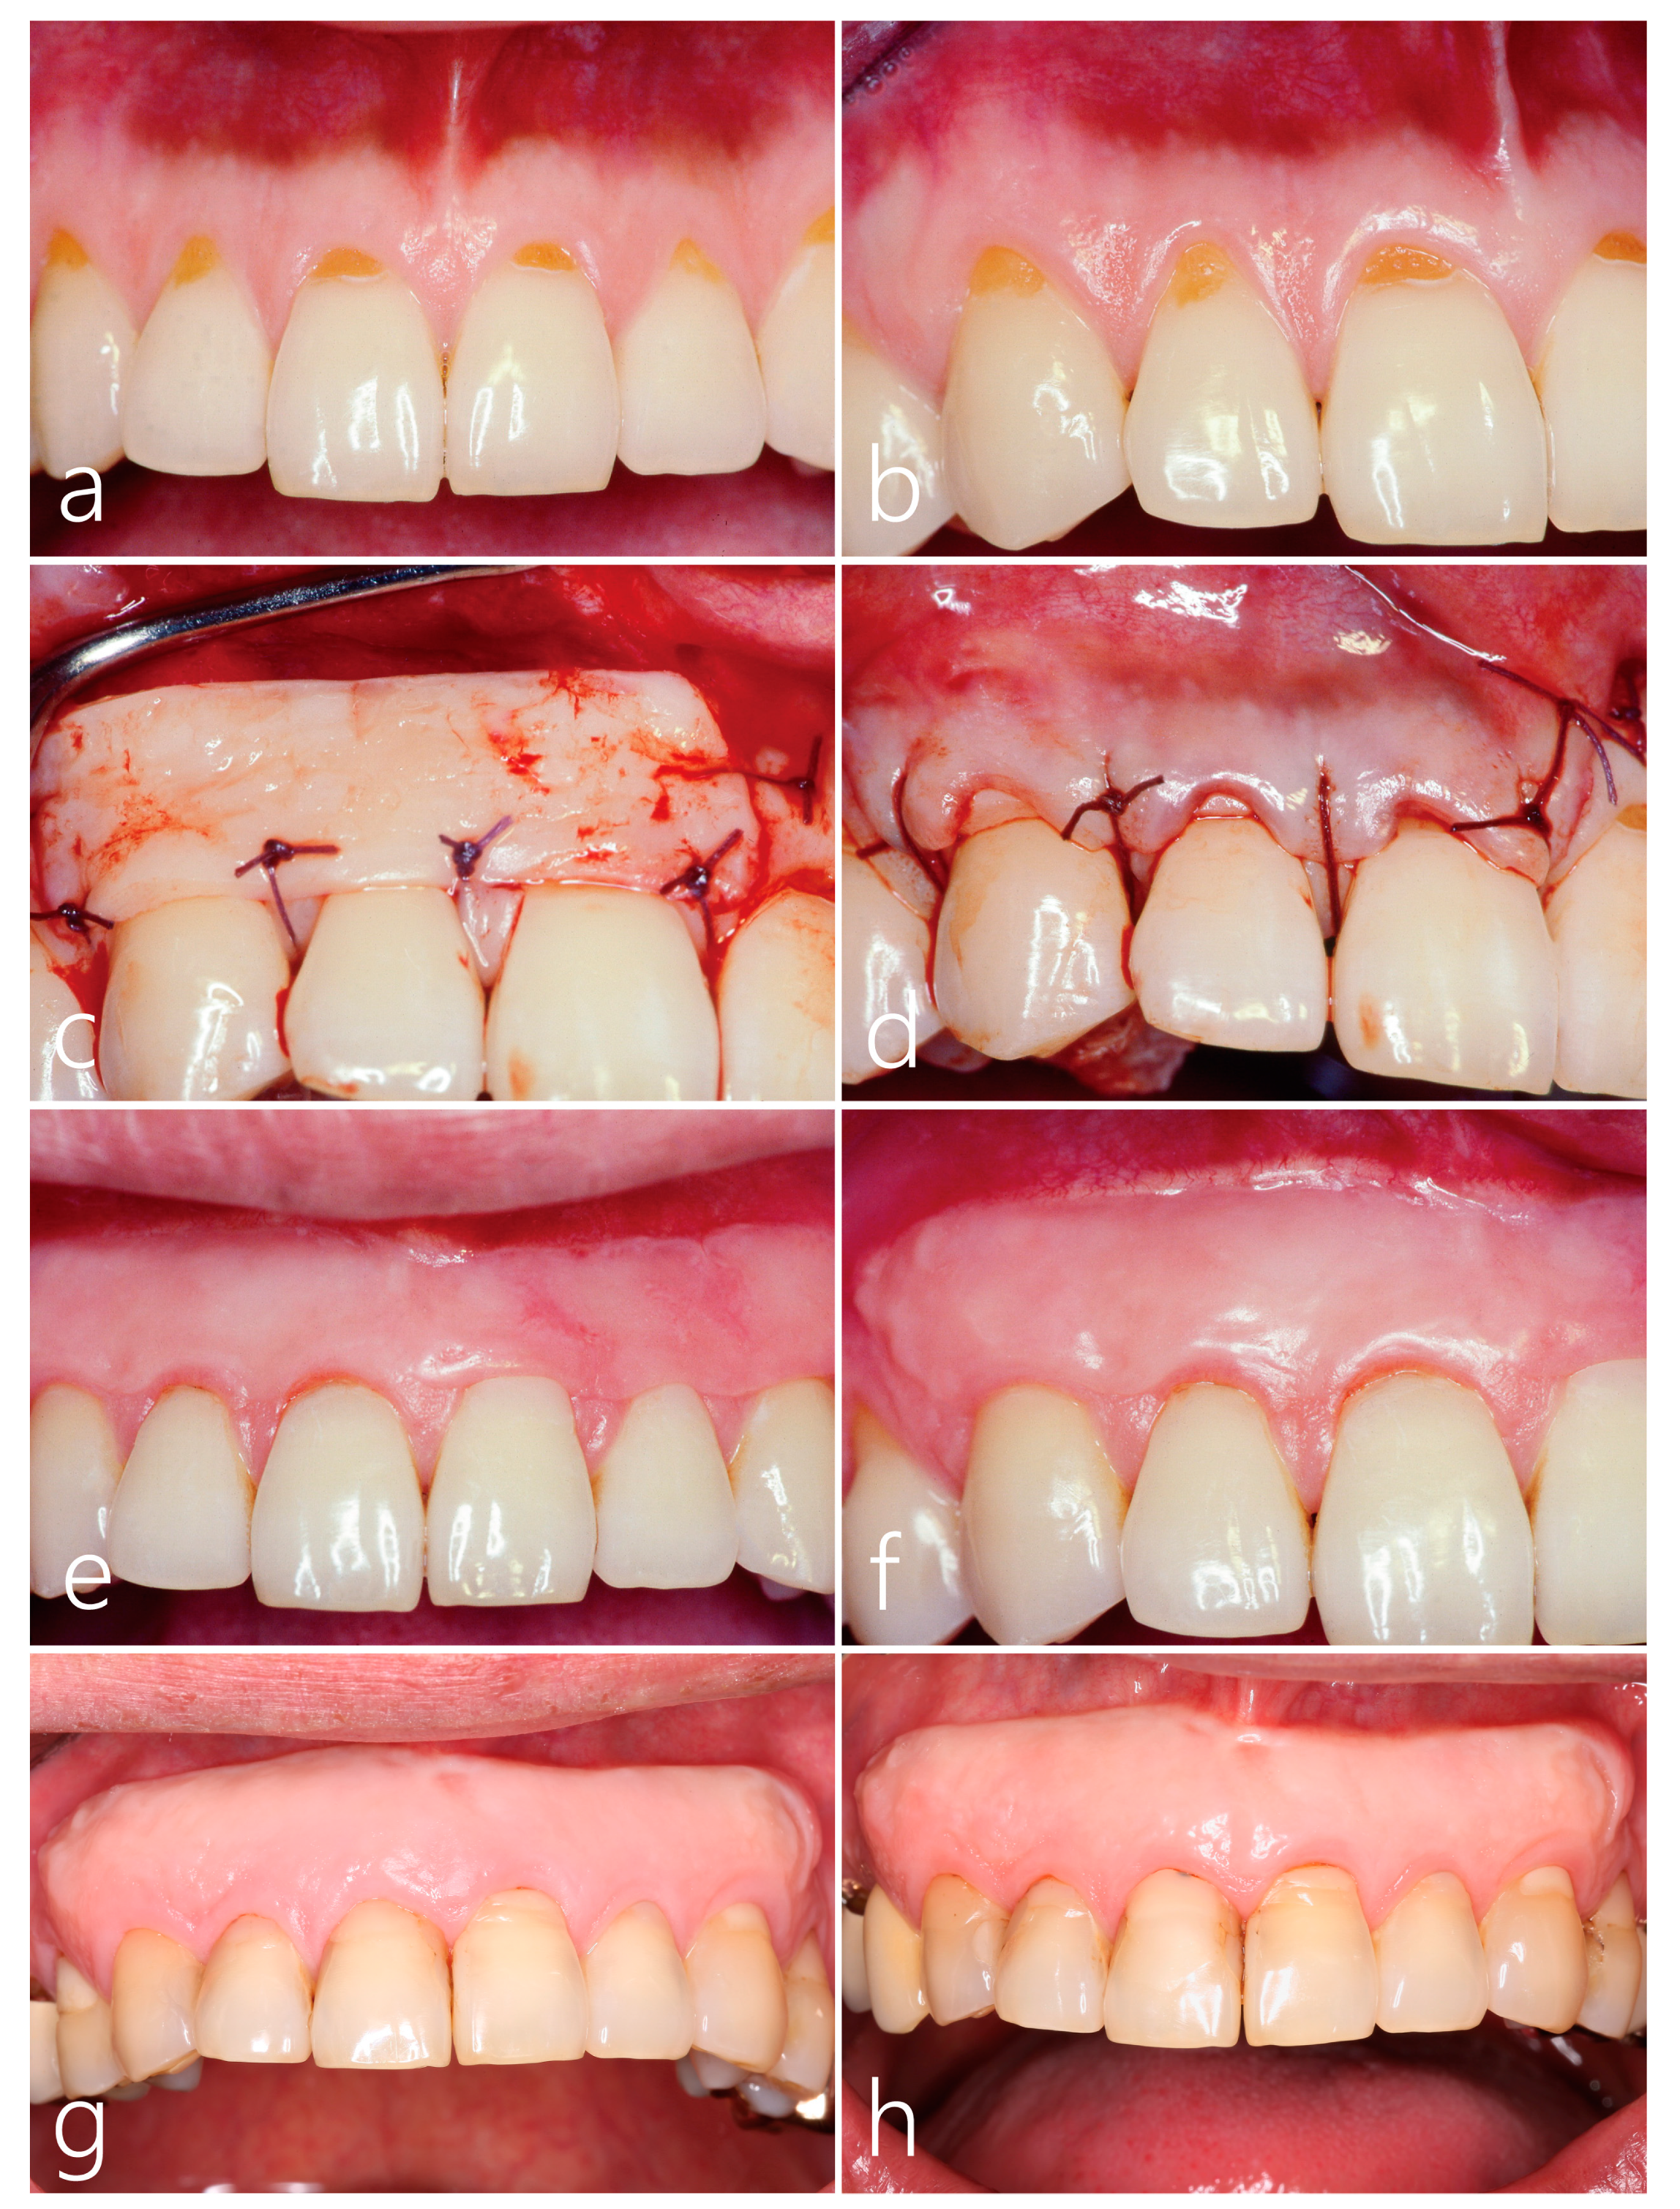

2. Case Presentation

Surgical Procedure

3. Results